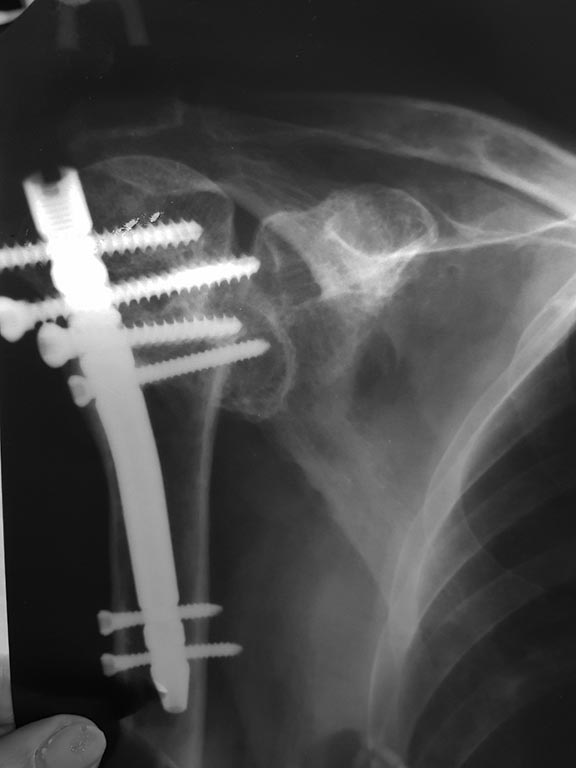

перелом плеча, состояние после металлосинтеза

Здравствуйте,больная - женщина 73 года. В ноябре 2017 года оскольчатый закрытый перелом правого плеча.

Была проведена операция, поставлен мет. стержень. Рука поднимается на 25 градусов. При любом шевелении боль. Травматолог уверяет, что все нормально и это просто плексит, но не верится. Повторной операции для замены сустава боимся по причине аллергии на многие медикаменты, отягощенной бронхиальной астмой, так же диагностированы энцефалопатия и сосудистый паркинсонизм. Возможно ли облегчение состояния без хир. вмешательства или малоинвазивным способом. Женщина адекватна, контактна. Спасибо

Самое доступное, что можно сделать, и что хоть как-то улучшит ситуацию - надо убрать стержень. Он выстоит, и при движениях присходит его соудаарение с акромионом. Минимум два винта выстоят из головки и травмируют суставную поверхность, препятствуют движениям.

По одной проекции полной картины не составить. Надо сделать снимки в других проекциях, а лучше КТ. Можно уже после удаления. Возможно, появятся какие-то еще предложения.